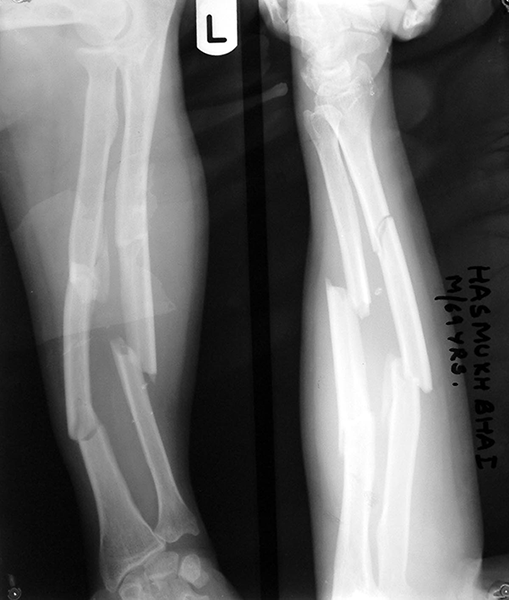

Case:6 Segmental Comminuted Fracture Radius

Patient, aged 75 years during morning walk tripped & had a fall following which he sustained injury to the left forearm. Closed reduction & interval fixation with Intra-medullary TEN nails was done in radius & ulna. Now he has full supination & pronation function of forearm.

Pre-Op

Post-Op